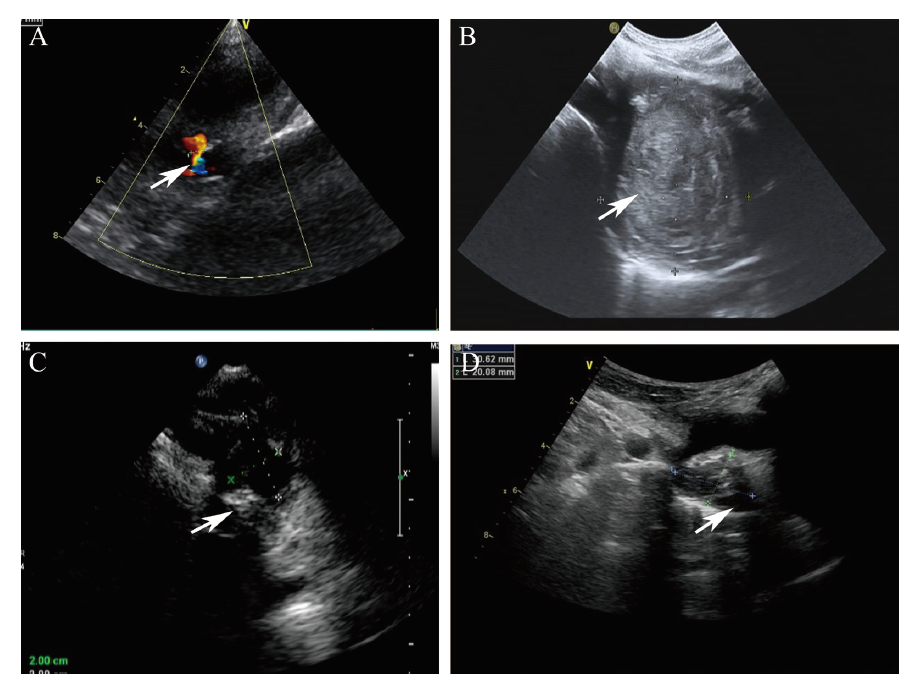

CT显示右上纵隔血肿,气管左偏(图1B),数字减影血管造影(DSA)造影发现右侧无名静脉侧壁有2 mm左右小孔活动性出血,颈部浅表静脉怒张(图1C),彩色多普勒超声(彩超)也显示类似结果(图2A)。

图2 一例血透患者右无名静脉损伤后超长时活动性出血的彩超图

注:A为2019年6月24日,无名静脉2 mm穿孔、活动性出血(箭头所示),持续1个月余;B为2019年9月5日,右侧无名静脉旁血肿(箭头所示)直径55 mm×47 mm,无活动性出血;C为2020年3月21日,右无名静脉旁血肿(箭头所示)30 mm×28 mm,钙化;D为2020年8月5日,右无名静脉旁血肿(箭头所示)30 mm×20 mm, 钙化。

诊断:慢性肾脏病5期;右无名静脉针刺伤伴活动性出血;纵隔血肿。患者因经济困难不同意置入覆膜支架止血治疗;为减轻动静脉内瘘建立后左向右分流对中心静脉产生的压力、减少出血,急诊行“右腕部动静脉内瘘结扎术”,以右侧股静脉TCC行无肝素血液透析,血压控制在正常范围,减少容量负荷,严密观察相关症状、体征,反复复查胸部增强CT和颈部血管超声1月余,患者症状无加重、胸部CT血肿无增大、颈部血管超声活动性出血停止(图2B)后转门诊;依然不定期检查胸部CT和血管超声,右纵隔血肿缓慢吸收变小,患者日常生活等无影响。13个月后彩超(图2C)及增强CT检查(图1D),右无名静脉闭合,纵隔血肿减小到2.9 cm×2.8 cm并部分钙化,予左腕部建立R-C AVF并顺利成熟使用。18个月后再次彩超示血肿进一步缩小、钙化(图2D)。